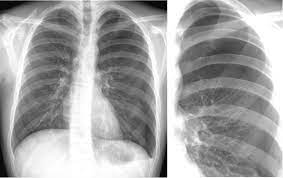

On an expiratory film, a pneumothorax will appear relatively larger, taking up a larger percentage of the thoracic cavity.

The typical effects of a fibrothorax are shown: The incidence is approximately 10 out of 100 000 residents per year. Therefore, it is mandatory to treat it safely. In this video, you'll learn how to identify when radiological pleura is abnormal and the key signs to look out for when trying to diagnose a pneumothorax. On an expiratory film, a pneumothorax will appear relatively larger, taking up a larger percentage of the thoracic cavity.

Of air is practically undetectable by physical examination, and one containing from 200 to 250 cc. Pneumo, luft, och thorax, bröstkorg) är ett tillstånd då ena eller båda lungorna komprimeras till följd av luftansamling i lungsäcken. When a pneumothorax is clinically suspected, we routinely perform cxr on both inspiration (as per usual) and expiration. In this video, you'll learn how to identify when radiological pleura is abnormal and the key signs to look out for when trying to diagnose a pneumothorax. On an expiratory film, a pneumothorax will appear relatively larger, taking up a larger percentage of the thoracic cavity. Louis duringthepast fewyears, therehave been many importantadvances in the diagnostic method of thoracic conditions. Scarcely less important is the selection of the positionmost favorable for obtaining information in fluoroscopicand Tillståndet uppstår ofta spontant hos unga och friska utan känd lungsjukdom, men kan drabba alla åldrar med eller utan tydlig orsak

Pneumo, luft, och thorax, bröstkorg) är ett tillstånd då ena eller båda lungorna komprimeras till följd av luftansamling i lungsäcken. Hence, if one considered selective pneumothorax as a sign of pathology in. Temaet er også relevant for andre helsefagutdanninger. Chest (1977), 71, 211 bilateral spontaneous pneumothorax with pulmonary metastases from synovial cell sarcoma harjit singh, nachhattar singh and ravinderpal kaur government medical college and rajindra hospital, patiala, punjab, india summary the association of bilateral spontaneous pneumothorax with pulmonary metastases is rare. Røntgen af thorax viser en luftlomme med en synlig visceral pleuralinie (konveks mod brystvæggen), nogle gange foreligger der også lidt pleuravæske 1 ved en mindre pneumothorax (kappepneumothorax) er afstanden fra pleura viscerale (lungekanten) til indersiden af brystvæggen mindre end 2 cm thoraxrøntgen med forskellige typer af pneumothorax Cannot be detected even by the roentgen rays. It occurs through an immediate disruption of the visceral pleura that results in an accumulation of air in the pleural space. Ennek következtében súlyos respiratoricus állapotromlás következhet be, amely mielőbbi orvosi. Distinctive variability in forms of effusions and to special methods. Maybe you would like to learn more about one of these? It entails few complications and little risk. Sekundärer spontanpneumothorax, wird durch lungenerkrankungen oder krankheiten anderer organe verursacht. When a pneumothorax is clinically suspected, we routinely perform cxr on both inspiration (as per usual) and expiration.

Røntgen af thorax viser en luftlomme med en synlig visceral pleuralinie (konveks mod brystvæggen), nogle gange foreligger der også lidt pleuravæske 1 ved en mindre pneumothorax (kappepneumothorax) er afstanden fra pleura viscerale (lungekanten) til indersiden af brystvæggen mindre end 2 cm thoraxrøntgen med forskellige typer af pneumothorax pneumothorax. Røntgen af thorax viser en luftlomme med en synlig visceral pleuralinie (konveks mod brystvæggen), nogle gange foreligger der også lidt pleuravæske 1 ved en mindre pneumothorax (kappepneumothorax) er afstanden fra pleura viscerale (lungekanten) til indersiden af brystvæggen mindre end 2 cm thoraxrøntgen med forskellige typer af pneumothorax